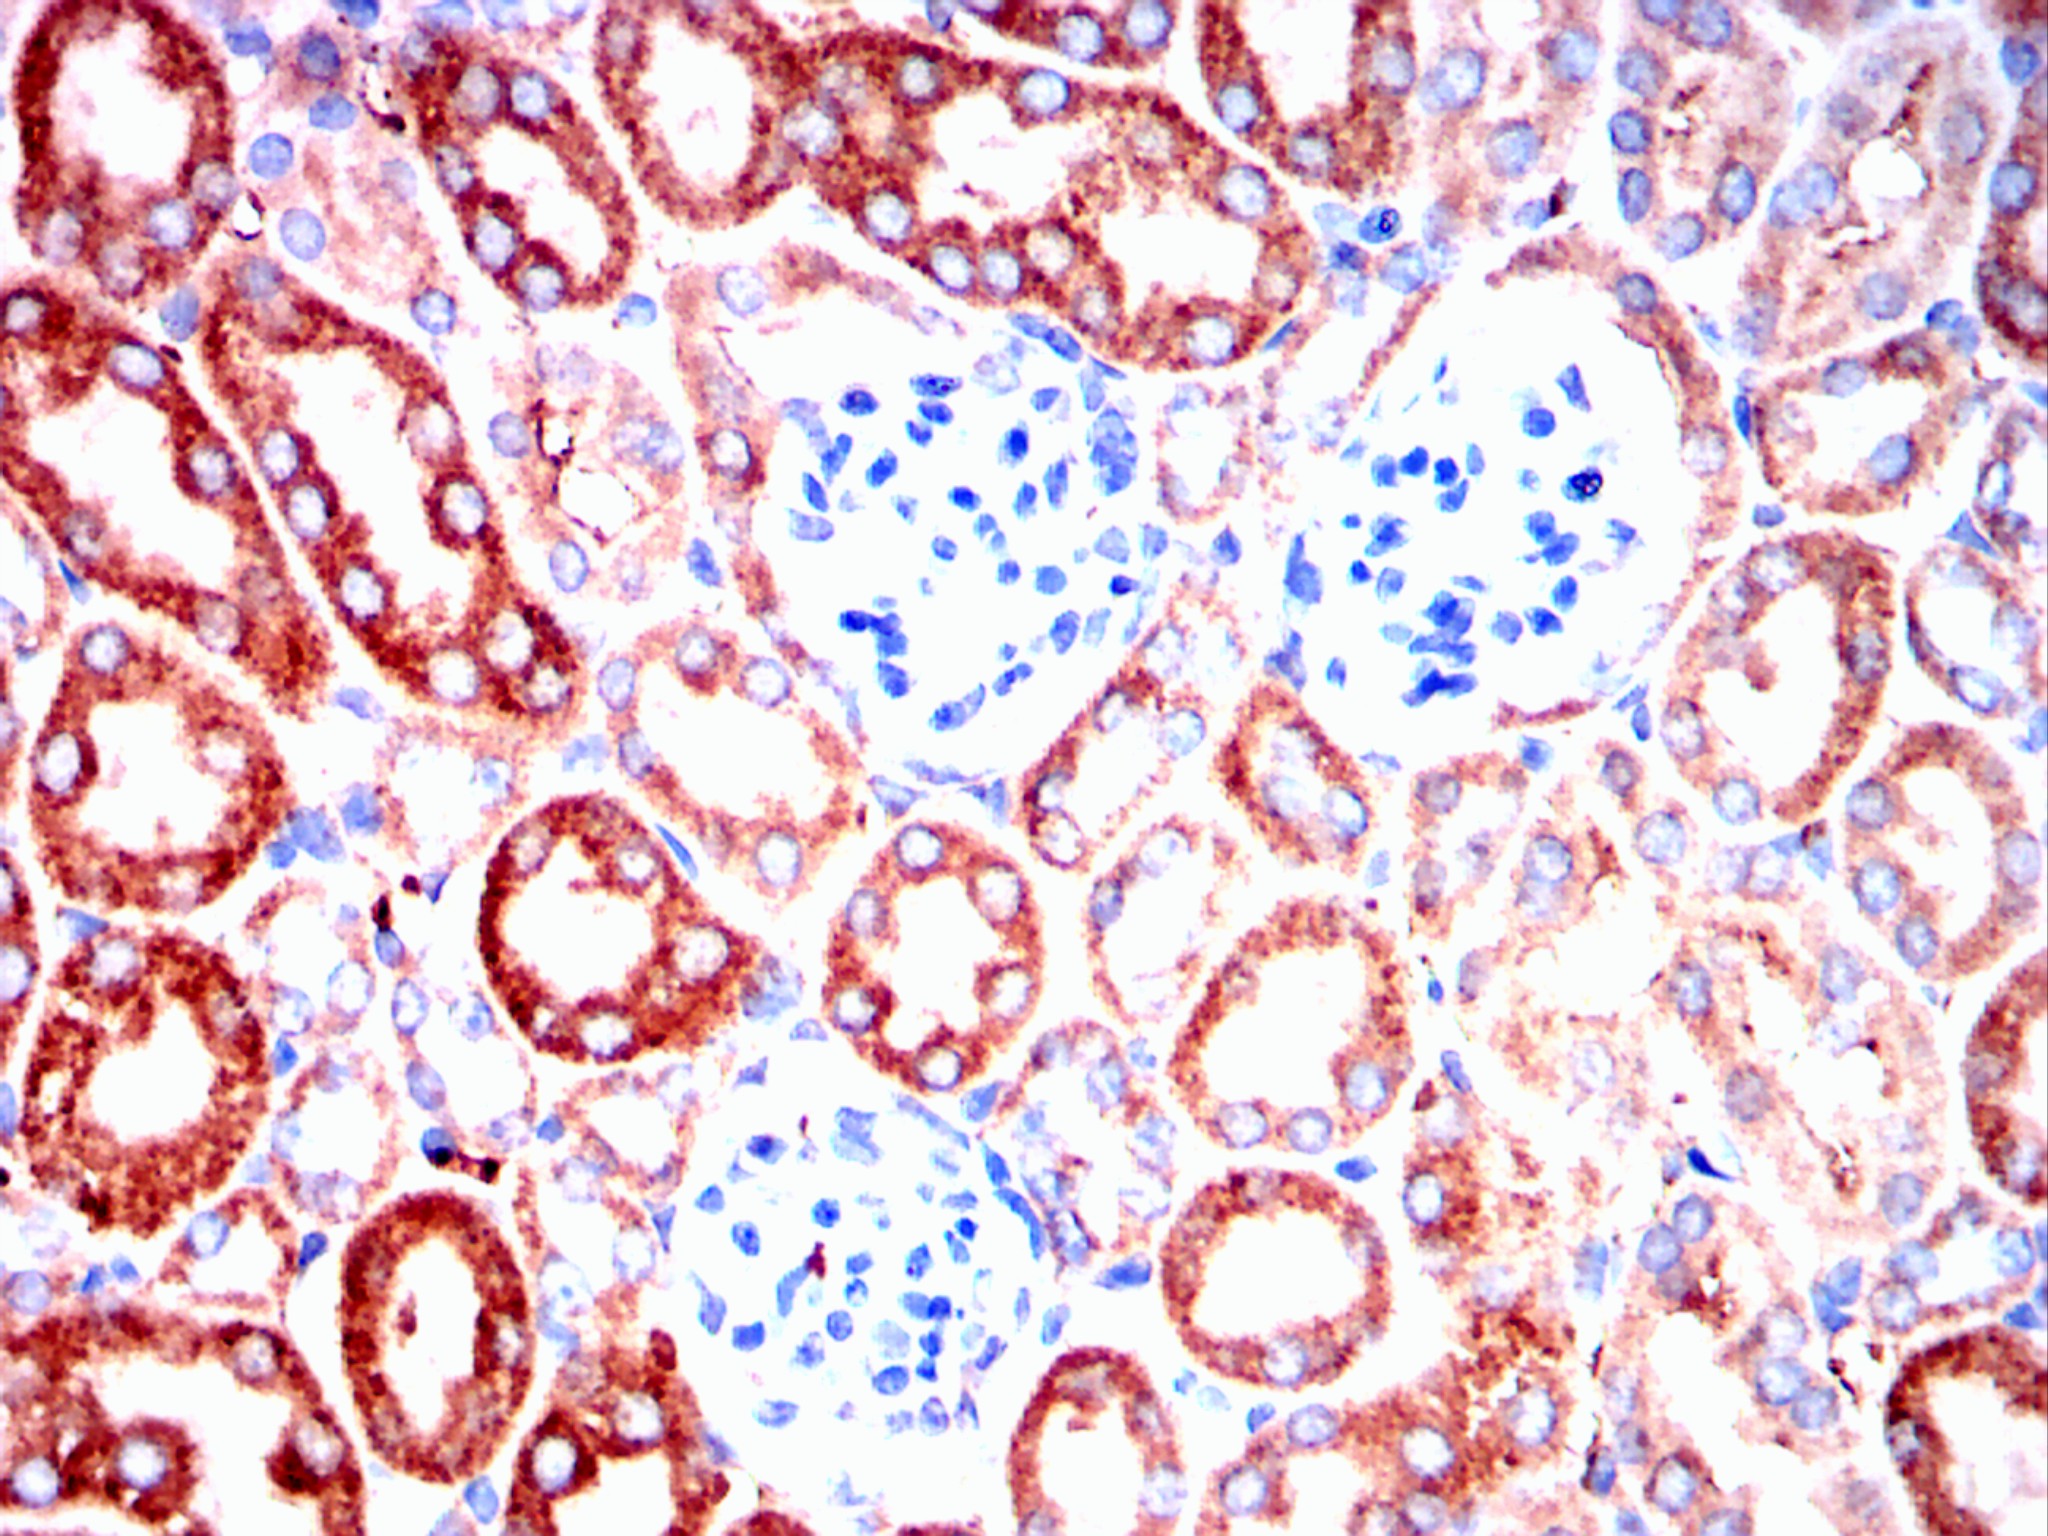

Immunohistochemical analysis of paraffin-embedded mouse kidney tissues using ERBB3 mouse mAb with DAB staining.

Immunohistochemical analysis of paraffin-embedded rat kidney tissues using ERBB3 mouse mAb with DAB staining.